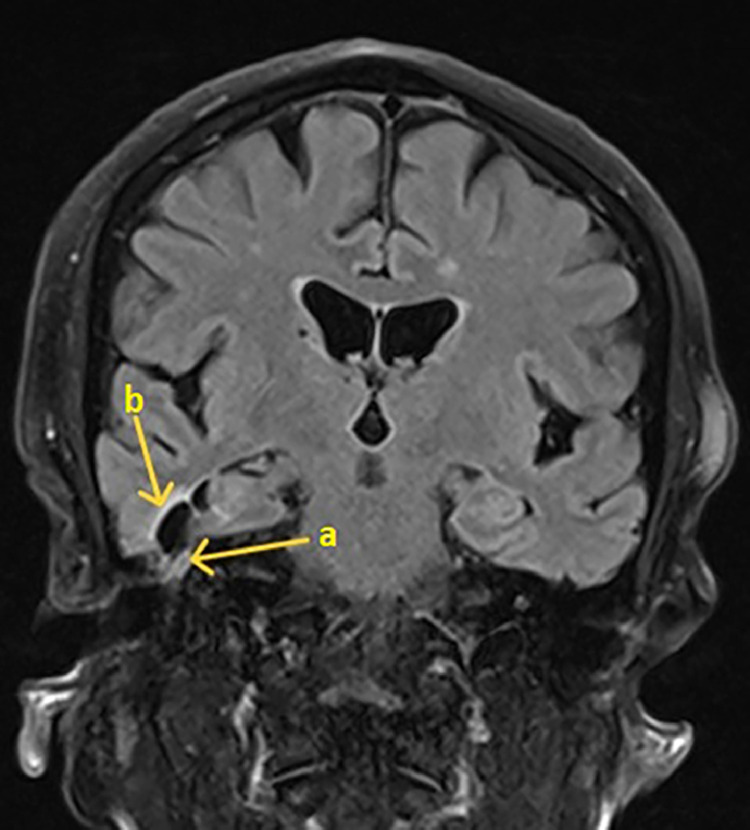

我们报告一例74岁女性头痛,发热,并间歇性右侧耳漏和鼻漏。她的鼻分泌物β -2-转铁蛋白检测呈阳性,证实脑脊液(CSF)泄漏。高分辨率CT (HRCT)显示右侧乳突、中耳和乳突空气细胞内的脑脊液缺损。钆增强脑MRI示侧脑室枕角弥散加权成像(DWI)高信号,DWI-表观弥散系数(DWI- adc)低信号,与脑室炎一致。经过六周的抗生素静脉注射后,她平静地康复了。病人接受手术修复骨缺损以防止复发。这是一例罕见的脑室炎合并自发性脑脊液泄漏的病例,没有现有的诊断标准,死亡率高。高临床怀疑辅助适当的影像学和多学科的方法来管理是必不可少的。

We present a case of a 74-year-old woman with headaches, pyrexia and intermittent right-sided otorrhoea and rhinorrhoea. Her nasal discharge tested positive for beta-2-transferrin, confirming a cerebrospinal fluid (CSF) leak. High-resolution CT (HRCT) mastoids showed a defect in the right tegmen, and CSF within the middle ear and mastoid air cells. A gadolinium-enhanced MRI brain showed high signal in the occipital horns of the lateral ventricles with diffusion-weighted imaging (DWI) and a low signal with DWI-apparent diffusion coefficient (DWI-ADC), consistent with ventriculitis. She made an uneventful recovery after 6 weeks of intravenous antibiotics. The patient had surgical repair of bony defects to prevent recurrence. This highlights a rare case of ventriculitis associated with a spontaneous CSF leak, with no existing set diagnostic criteria, and high mortality. High clinical suspicion aided by appropriate imaging, and a multidisciplinary approach to management are imperative.